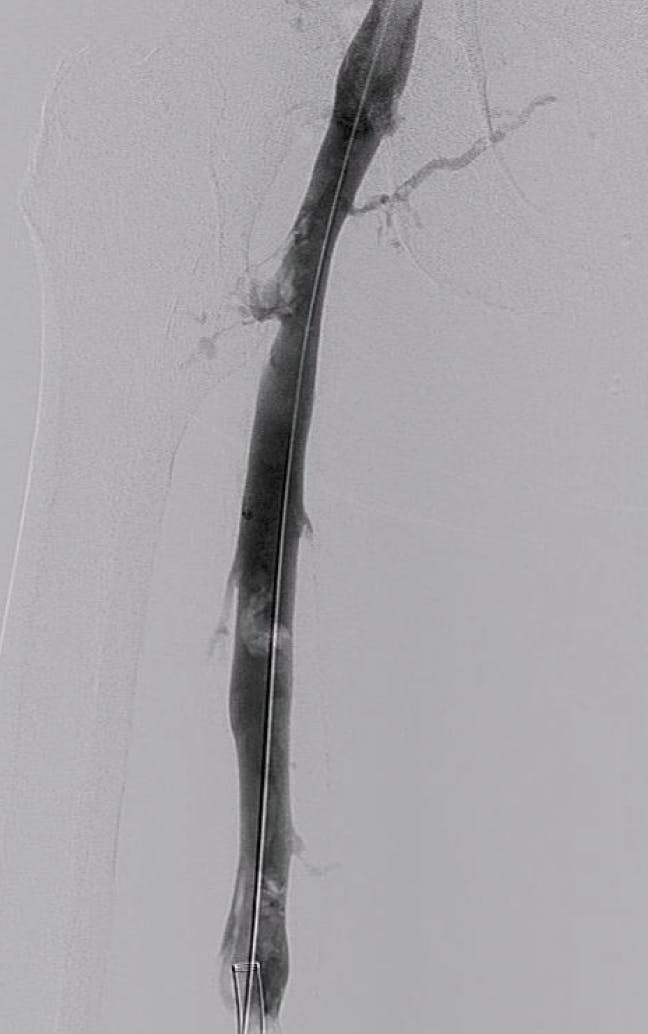

Figure 1. Preprocedural venogram.

The patient was placed on the table in the prone position. Access was then gained in the popliteal vein and a 16-F, 13-cm Flexor Check-Flo Introducer (Cook Medical) was placed. The Lightning Flash catheter was pulled and advanced through the sheath until the tip was at the face of the occlusion. Once at the face of the thrombus, the flow switch was flipped on to initiate aspiration power. On the first pass, macromovements were utilized to advance the tip of the catheter past the occlusive lesion. Ensuing this run, images were obtained. Venography confirmed that 60% of the clot burden was cleared from the initial pass. A few additional passes with the catheter were performed until complete thrombus resolution was achieved in the iliofemoral segment (Figure 2 and Figure 3), with a total aspiration time of 12 minutes.

Figure 2. Final venogram.